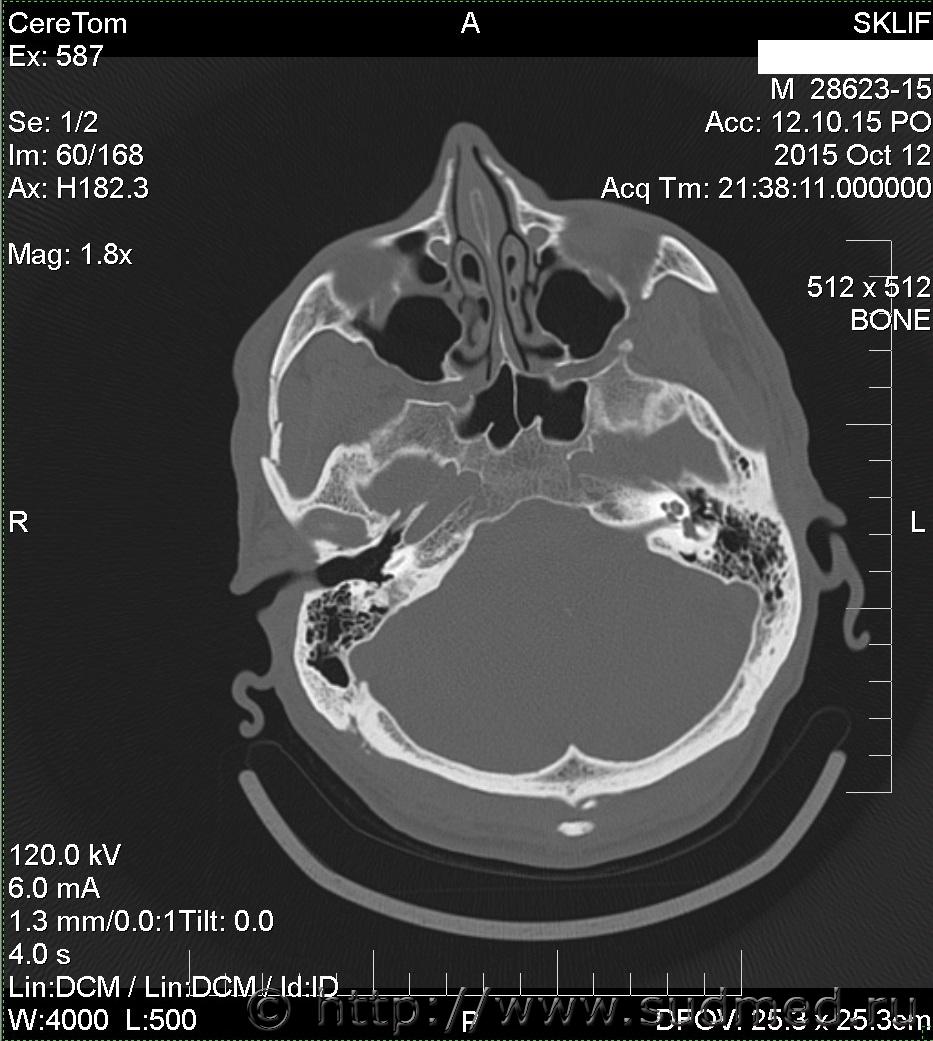

На Ленинградском вокзале меня избил охранник. Что-то я не то ему сказал, что-то он не то понял. В результате у меня множественный перелом скуловой дуги со смещением справа. Я инвалид 2 гр. Больничный не брал.

множественный перелом скуловой дуги со смещением справа

Вред здоровью средней тяжести. В соотвествие сп.7.1 приложения к Приказу Минздравсоцразвития от 24.04.08г. №194н.